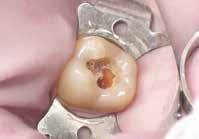

gyökér meziális felszínét perforálta. A lézió kerek és szimmetrikus volt, amely gyulladásos típusra utalt. Az oszteolitikus terület fókusza a perforáció közelében helyezkedett el (2. ábra). A csontban lévő lézió és a gyökérperforáció az endodonciai kezelés sebészi kiegészítését tette szükségessé. Ennek megfelelően az egy ülésben történő gyökérkezelést követően

– ugyanazon ülésben – sebészi beavatkozással egészítettük ki. Helyi érzéstelenítést követően megtörtént a hozzáférési nyílás kialakítása. A fogbélkamrát egy gyémánt felszínű ultrahangos eszköz segítségével kitisztítottuk és megfelelő formára alakítottuk. A fogbélkamra tisztítása során nátrium-hipokloritot alkalmaztunk, és emellett a

gyökércsatornában lévő pulpát is részlegesen eltávolítottuk. A sebészi feltáráshoz szükséges metszést a frenulum mellől indítottuk, majd intrasulcularisan, papillakímélő módon a szemfogig vezettük. A lebeny felemelését követően a csontos falú üregből a granulációs szövetet egy éles exkavátor segítségével eltávolítottuk.

A gyökércsatorna feltágítását és tisztítását hagyományos kemomechanikai protokoll szerint végeztük. Először passzívan levezetett kézi tűk segítségével a gyökércsatornát teljes munkahosszon szondáztuk, ezt követően gépi tágítókkal feltágítottuk, ezalatt nátrium-hipoklorittal öblítettünk, amelyet manuális agitációval aktiváltunk. A gyökércsatorna méretre történő tágítását követően, a következő átöblítőszereket alkalmaztuk: 3 percen keresztül ultrahanggal aktiváltunk 5,25%-os NaOCl oldatot, amelyet közben többször frissítettünk a csatornában, majd váltott átöblítés (17%os EDTA, 5,25%-os NaOCl) a smear layer eltávolítása céljából. Végső átöblítésként 5 percen keresztül ismét 5,25%-os NaOCl oldatot alkalmaztunk, amelyet ultrahanggal aktiváltunk és folyamatosan cseréltünk. A kemomechanikai megmunkálás és az átöblítőszerek alkalmazása során az elszívást a reszorbciós üreg széléhez helyeztük annak érdekében, hogy a kifolyó kémiai hatású szerek ne tudják a környező csont állományt roncsolni.

A gyökértömés elkészítése során meleg vertikális kompakciós technikát alkalmaztunk, sealerként pedig CeraSeal-t (Meta Biomed; 3. ábra) használtunk. A reszorbciós üreget Biodentine-nel (Septodont; 4. a–b ábra) töltöttük fel. A reszorbcióval érintett területtől koronális irányba elhelyezkedő csatornaszakaszt pedig tisztán meleg guttaperchával kezeltük. Ezt követően a lebenyszéleket visszafektettük, és varratok behelyezésével eredeti pozíciójuknak megfelelően rögzítettük. A koronai részt kompozit tömőanyag segítségével állítottuk helyre. Kontrollvizsgálatra 5, illetve 30 hónappal később került sor (5. ábra). A csontos telődés jelei már 5 hónap után észlelhetők voltak (6. a–c ábra). A 30 hónappal később végzett kontroll során sem találtunk csontban lévő lézióra, törésre vagy egyéb pathológiás elváltozásra utaló jeleket (7. a–b ábra)